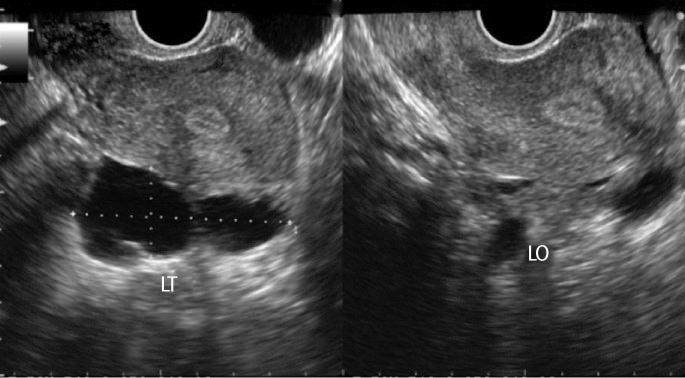

Many studies have demonstrated that hydrosalpinx has a detrimental effect on the outcome of IVF. Treating hydrosalpinges prior to the IVF procedure in women with hydrosalpinges is thought to improve the likelihood of successful IVF outcome. Vaginal ultrasound-guided aspiration of hydrosalpinx fluid (HSF) with injection of the sclerosing agent in situ might be simpler than invasive procedures like salpingectomy. Therefore, we carried out a retrospective study on the effects of ultrasound-guided HSF aspiration and injection of the sclerosing agent of ultrasonically diagnosed hydrosalpinx on IVF outcome.

许多研究表明,输卵管积水对体外受精(IVF)结局有不利影响。对于患有输卵管积水的女性,在IVF手术前治疗输卵管积水被认为可提高IVF成功的可能性。阴道超声引导下抽吸输卵管积水液(HSF)并原位注射硬化剂可能比输卵管切除术等侵入性手术更简单。因此,我们对超声引导下HSF抽吸及注射硬化剂治疗超声诊断的输卵管积水对IVF结局的影响进行了一项回顾性研究。